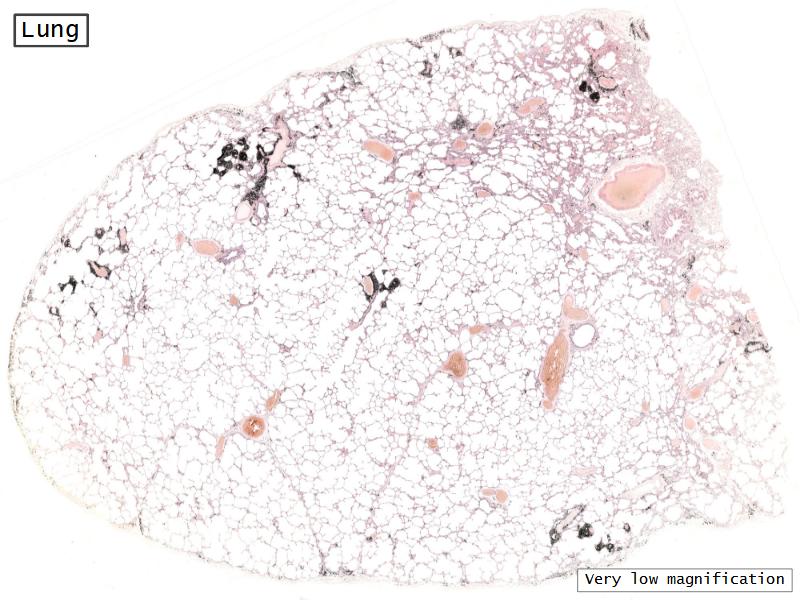

Slides: Respiratory System

- Slide 72 & 74: Lung

Lungs